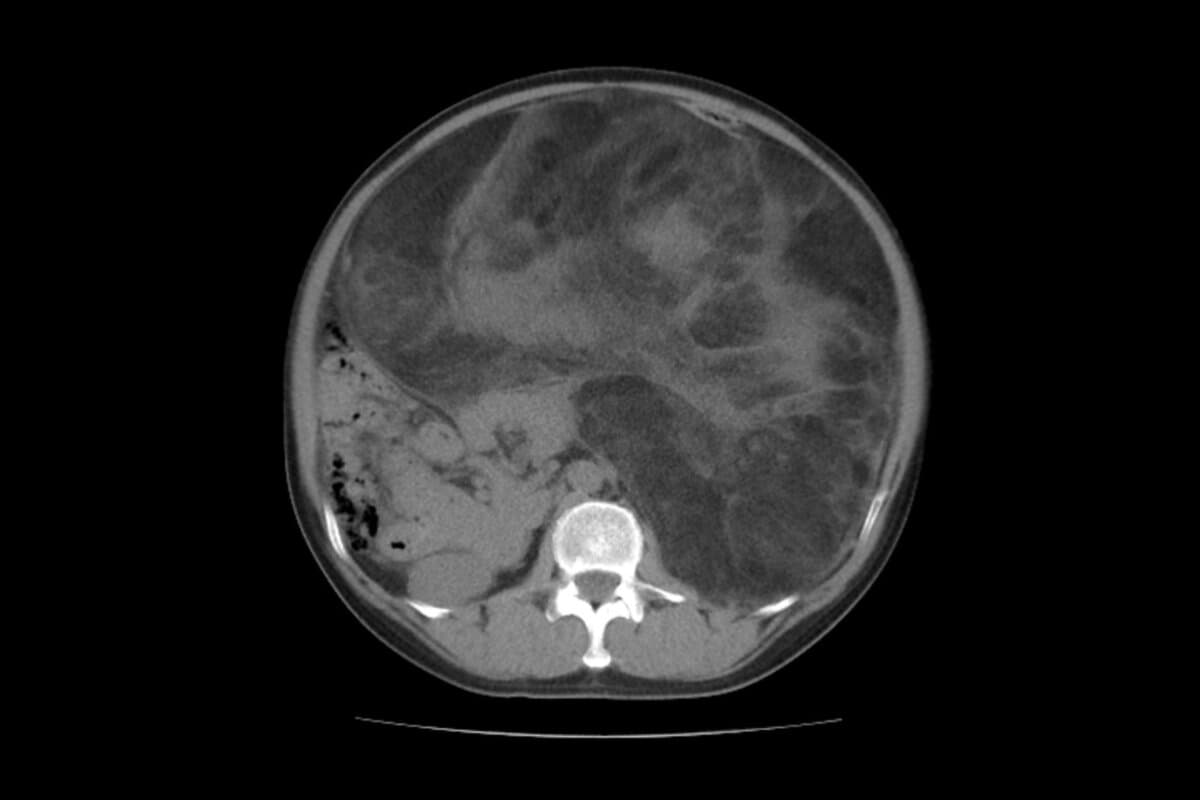

Fallbericht: Riesiges retroperitoneales dedifferenziertes Liposarkom

Der aussergewöhnliche Fall eines über zehn Kilogramm schweren, retroperitonealen, dedifferenzierten Liposarkoms zeigt eindrucksvoll die Herausforderungen in der Diagnostik und Therapie dieser seltenen Tumorentität, schreiben Dr. Huey Bing Chua und Kollegen, Universiti Kebangsaan, Kuala Lumpur, Malaysia, in Sec. Surgical Oncology.